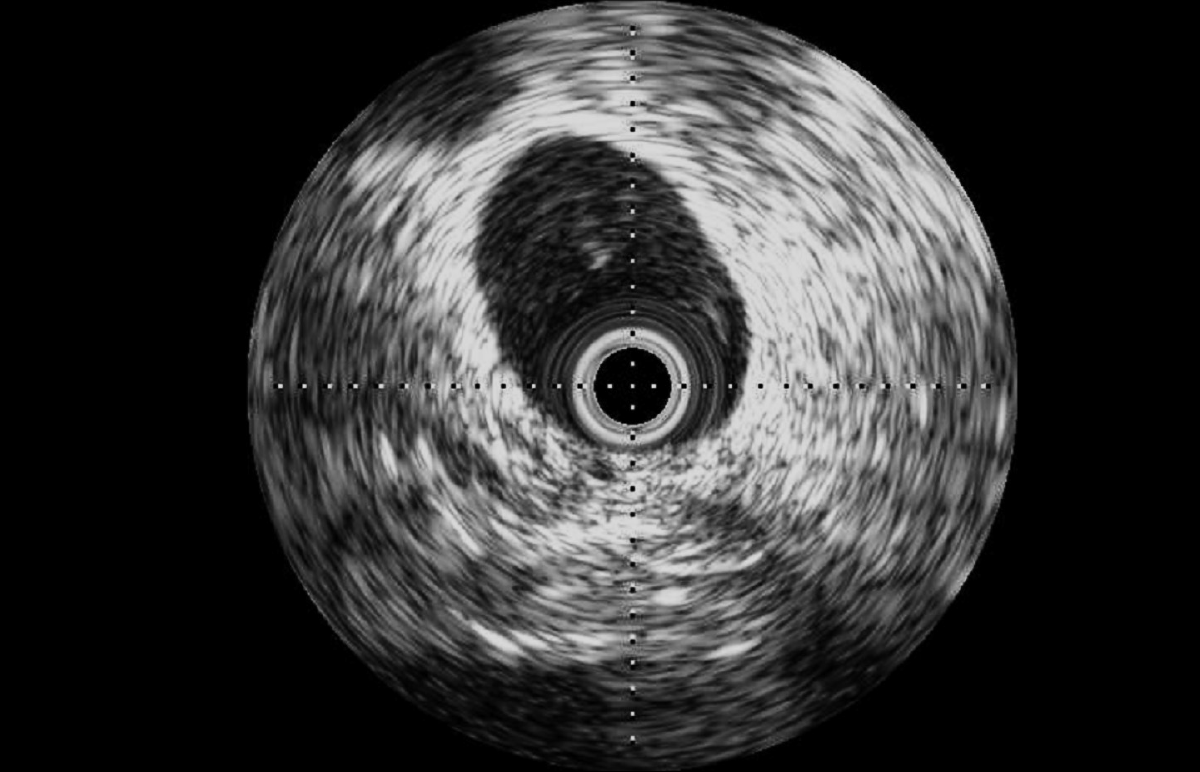

Intravascular ultrasound (IVUS): external iliac vein of a 100 kg-male ovine

• Intravascular ultrasound (IVUS) may be a valuable tool to evaluate vessel morphology and size before implantation, guide device implantation, and assess long-term device position and safety.

• A complementary technique, optical coherence tomography (OCT) is an imaging modality that uses near-infrared light to provide high-definition images with higher spatial resolution and tissue penetration than IVUS, and our imaging specialists can help determine which technology is best for your needs.